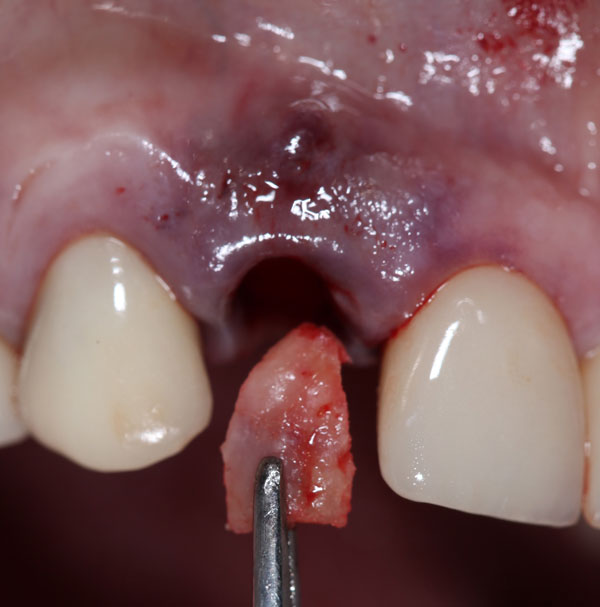

The Immediate Dentoalveolar Restoration (IDR) is a surgical and prosthetical technique established to broaden indications for immediate loading on individual teeth. In this way, tissue losses with varied extensions are reconstructed in the same surgical session of implant placement and provisional crown installation, reducing the number of interventions and keeping predictability on esthetic aspects. The IDR protocol was developed more than 12 years ago from the need to minimize the treatment time

In the course we discuss the scientific basis, the step-by-step technique, indications and bone biology. The IDR technique, which advocates minimally invasive surgery, flapless procedures, is presented as a viable and reproducible alternative.

It is presented several cases, which showed one or more compromised socket walls of the tooth involved, with or without changes of the gingival margin, some with more than 12 years of clinical, radiographic and CT scan follow-up.

IDR protocol using cortico-cancellous graft

Maxillary tuberosity as the main donor area of bone and soft tissue grafts

e. Learn how to harvest an autogenous bone graft from maxillary tuberosity.

f. Management of the graft and complete reconstruction of the alveolar defect.